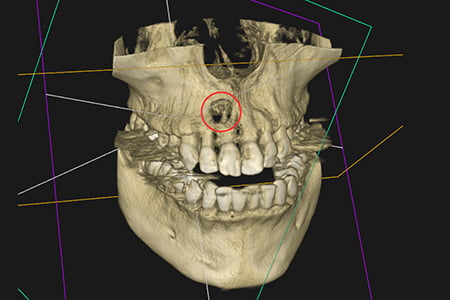

治療例3

| 症状 | 左上の前歯が急に疼く様になった |

|---|---|

| 治療方針 | 大きな骨欠損を認められる為、精密根管治療を行い骨欠損部位が改善するか経過を追う |

| 治療期間 | 10ヵ月 |

| 治療費用(税込) | ¥468,600 ※2歯分 |